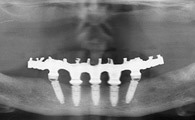

IMPLANTOLOGIE : LES BRIDGES FIXES COMPLETS MANDIBULAIRES